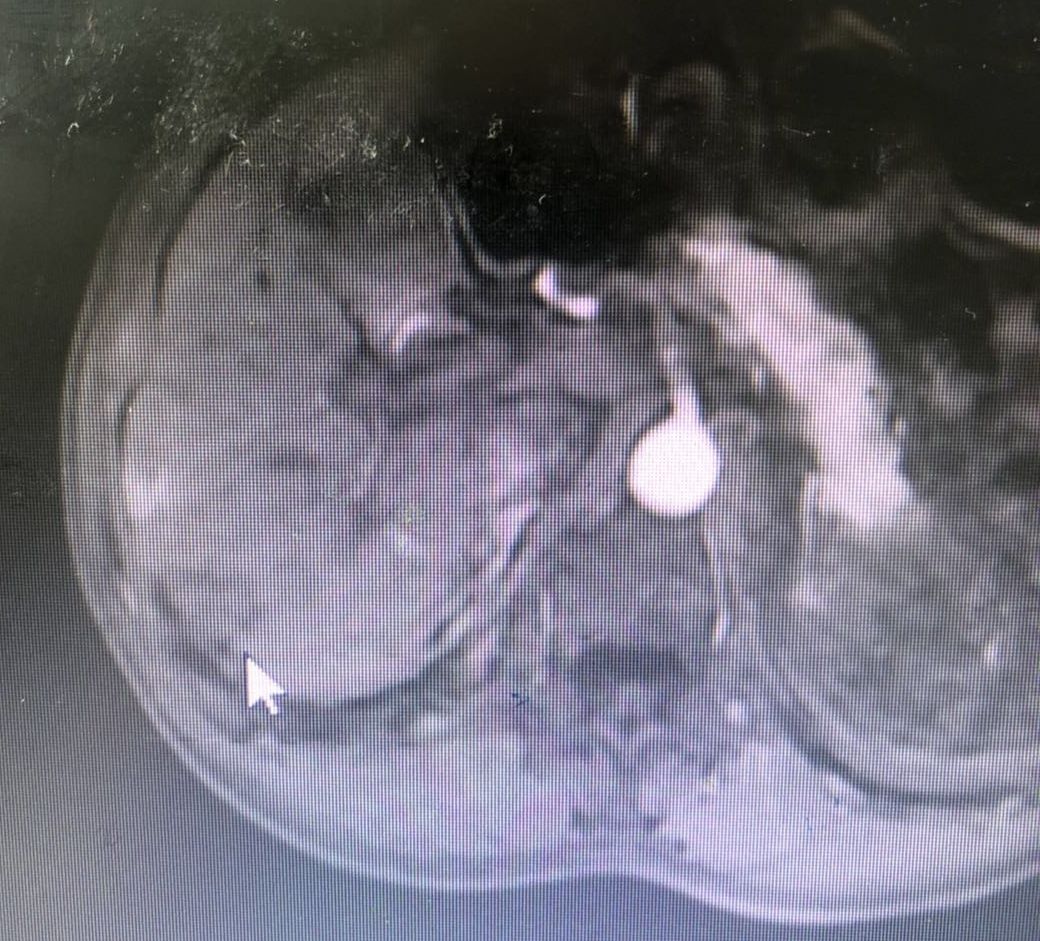

得以消融的病灶

2017年1月,在完善手术方案和术前检查后,王剑飞和黄忠炎在超声引导下为沈大伯进行了肝肿瘤射频消融术。手术和术后恢复都十分顺利,他很快出院了,并定期回到科室复查,病情一直保持稳定。

这是沈大伯最新的复查结果——肝脏上又发现两个新发结节!这对沈大伯而言几乎如霹雳一般。

很快,正如那个笃定的笑容,沈大伯第二次微波消融术毫无意外地完成了,且仅过了三天就安然出院了。“两年时间,你们的技术又进步了好多,本来以为只能依靠手术或者放化疗了,没想到微创介入两次给了我新生的希望!”沈大伯喜出望外,激动不已。